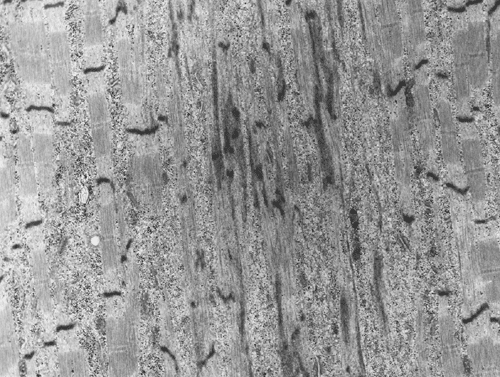

A biopsy was performed. The followings are representative photomicrographs of the biopsy material.

Pathology of the case:

| A. | B. |